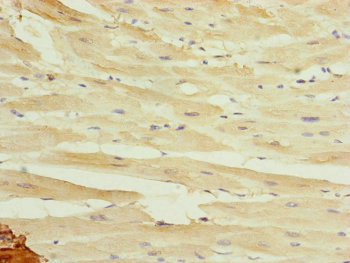

圖片:

應(yīng)用范圍:ELISA, IHC

Application Recommended Dilution IHC 1:20-1:200 -